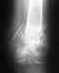

1)По снимку не видно, что есть какие-то большие проблемы. Для полноты картины лучше посмотреть на вторую проекцию. Отсутствие сращения месяца в 4-6 может уже быть основанием для каких-то активных действий.

2)выстояние винтов обычное, проблем не создает. 3)лечить надо не снимок, а пациента. То есть сейчас отломки фиксированы, надо восстановить амплитуду движений в локтевом и лучезапястном суставах, ротацию предплечья. "Правильные методы электофореза" существуют в той же мере, что и "ускорители беременности". Даже если не будет сращения через разумное время, что после накостного остеосинтеза случается Ё в 10-15% случаев из-за ухудшения кровообращения фрагментов при их обнажении, это не фатально. А вот вовремя не восстановленная функция суставов может оказаться потерянной безвозвратно.